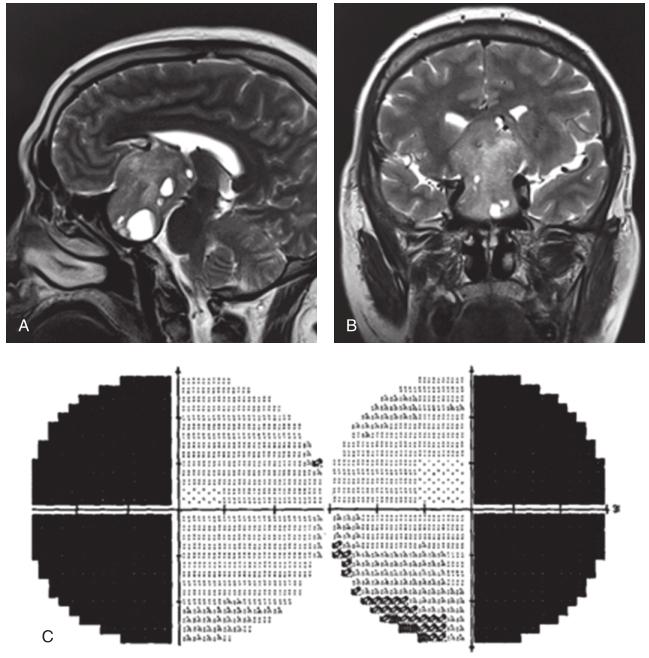

◎ 如视野检查发现单眼或双眼颞侧偏盲,须进行垂体或眼眶MRI检查(急诊行垂体CT即可),有助于明确病变性质(图1)。

图1垂体瘤

A,B.头颅MRI,显示鞍区占位;C.视野表现为双眼颞侧偏盲